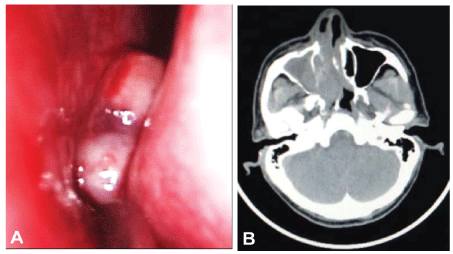

A 52-year-old man complained of nasal obstruction and intermittent rhinorrhea with blood for one week. Nasopharyngo-fiberoscope examination showed that an exophytic pinkish mass with smooth surface was observed in his right nasal cavity. The mass was fragile and bleed easily (Figure 1A). A computed tomography (CT) scan of the nose and paranasal sinuses demonstrated an irregular soft tissue mass filled in the right nasal cavity, ethmoid sinus and maxillary sinus with nasal septum deviation to the left. The lesion extended into the medial and posterior wall and resulted in bone destruction (Figure 1B). No mass was found in nasopharyngeal region. There was no lymph node enlargement or hepatosplenomegaly. Laboratory and bone marrow examination were normal.

Figure 1: (A) Nasopharyngo-fiberoscope examination showed an exophytic pinkish mass with smooth outline in right nasal cavity; (B) CT scan demonstrated irregular soft tissue mass in the right nasal cavity, ethmoid sinus and maxillary sinus with nasal septum deviation to the left. The lesion extended into the medial and posterior wall and resulted in bone destruction